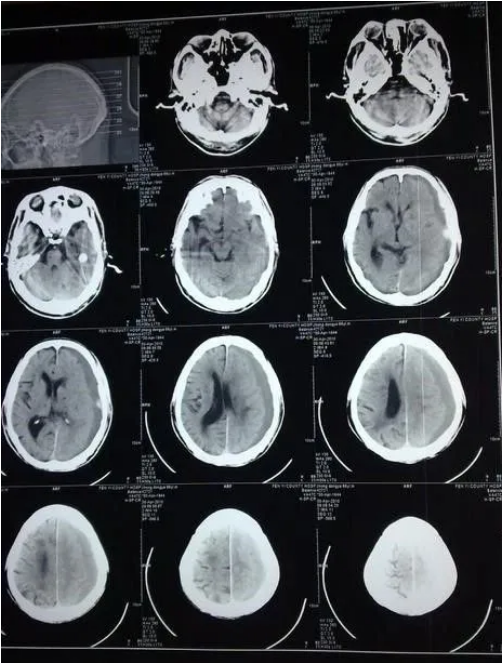

高血压脑出血,顾名思义,由于高血压造成的脑出血,其实高血压脑出血不是一日之功,首先人的脑血管随着年龄会发生粥样硬化,尤其当合并高血压、糖尿病、高脂血症、吸烟等危险因素时,加上人的脑血管较全身其它血管管壁要薄,由于情绪、天气、便秘、屏气等动作导致血压突升,从而引发硬化的血管发生破裂。最常见的破裂血管是起源于颅底大血管的穿通支,主要供应人的基底节、丘脑、桥脑等部位,因此,高血压脑出血最常见于基底节区(图1)、丘脑、桥脑(图2)等部位,也可见于小脑、大脑皮层、脑室等。由于出血部位深在,且位于人脑的重要功能区,因此高血压脑出血有着极高的致死率和致残率,而且手术效果不佳。所以,预防比治疗显得更为重要,随着高血压、糖尿病、高脂血症的逐渐低龄化,高血压脑出血也不再是老年人的专利,中青年的高血压脑出血也不算罕见了。如果发现高血压、高血脂及高血糖一定要及时治疗,防患于未然。

而另外一种脑出血——动静脉畸形造成的脑出血则更多见于青年人。顾名思义,所谓畸形是指脑血管的先天发育异常,准确的说是脑内的一团相互缠绕的管径大小不同的异常血管团,加上供血动脉和引流静脉构成,简称AVM(图3,图4)。AVM的供血动脉和引流静脉之间无毛细血管而直接沟通形成数量不等的窦道,血液由供血动脉流入畸形血管团,通过窦道直入静脉,由于缺乏毛细血管结构,血管壁发育不完善,加上长期血流冲击,易在畸形图案内部出现微小动脉瘤,造成出血,AVM的出血常见于大脑皮层,也可以见于脑室旁、侧裂等部位,除了出血,AVM患者还可能以癫痫或头疼做为首发症状,对于不合并高血压的年轻人的脑出血一定要警惕AVM。AVM的治疗方法主要有手术切除和介入栓塞治疗,具体哪种方法需要医生根据AVM的部位、大小、造影结果决定。

前面两种脑出血一般都表现为脑实质内的出血,还有另外一种更为凶险的脑出血——自发性蛛网膜下腔出血(图5),是指发生于蛛网膜下腔的自发出血,这种出血多数都是由于大脑动脉的动脉瘤(图6)破裂造成,动脉瘤一般发生于人脑的大血管,这些大血管进入颅内后先走形于脑底部的蛛网膜下腔内,与颅外血管比较,脑血管中膜层和外膜缺乏弹力纤维,中层肌纤维少、外膜薄、内弹力层更加发达隆凸,在蛛网膜下腔内支撑结缔组织少,以及血液动力学改变,均可促使进动脉瘤形成。获得性内弹力层的破坏是囊性脑动脉瘤形成的必要条件,动脉硬化、炎性反应和蛋白水解酶活性增加促使内弹力层退变。高血压并非动脉瘤的主要致病因素,但能促进囊性动脉瘤形成和发展。简单的说,颅内动脉瘤就像汽车轮胎的鼓包,这种鼓包一般是由于动脉炎症或长期血流冲击造成。由于动脉瘤壁缺乏完整的血管结构,因此容易破裂出血,由于动脉瘤一般发生于颅内的大血管,因此动脉瘤一旦破裂出血一般都很凶险,死亡率大约25%,幸存者致残率也接近50%,对于典型的蛛网膜下腔出血应高度怀疑颅内动脉瘤,如有条件尽早夹闭或栓塞动脉瘤,杜绝其再次破裂出血是挽救患者的唯一方法。

还有一种常见于老年人的脑出血叫慢性硬膜下出血(图7),这种出血一般发展缓慢,多有轻微的外伤史,有的外伤很轻微甚至无法回忆,因此一般只有一半的患者能回忆起有近期的外伤史,比如摔倒、头部磕磕碰碰等。慢性硬膜下血肿多发生于外伤后数周至数月内,老年人多见,与老年人脑萎缩,脑组织相对容易移位有关系,发生隐匿,早期症状表现轻微,比如头痛、精神差等,严重可能有走路不稳或肢体无力,因此,对于有近期外伤史的老年人,一旦出现肢体无力、走路不稳等,一定带老人查个头颅CT来除外慢性硬膜下血肿,慢性硬膜下血肿治疗效果一般较好,多数患者只需要一个简单的钻孔引流就可以治愈。因此,对于慢性硬膜下血肿,应早发现早治疗,预后一般良好。